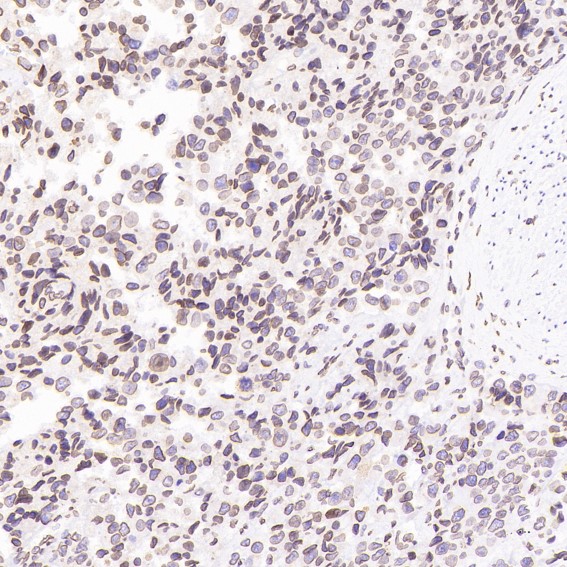

Immunohistochemical analysis of paraffin-embedded Human glioblastoma, using the Antibody at 1:100 dilution.

mmunohistochemical analysis of paraffin-embedded Human prostate cancer, using the Antibody at 1:100 dilution.